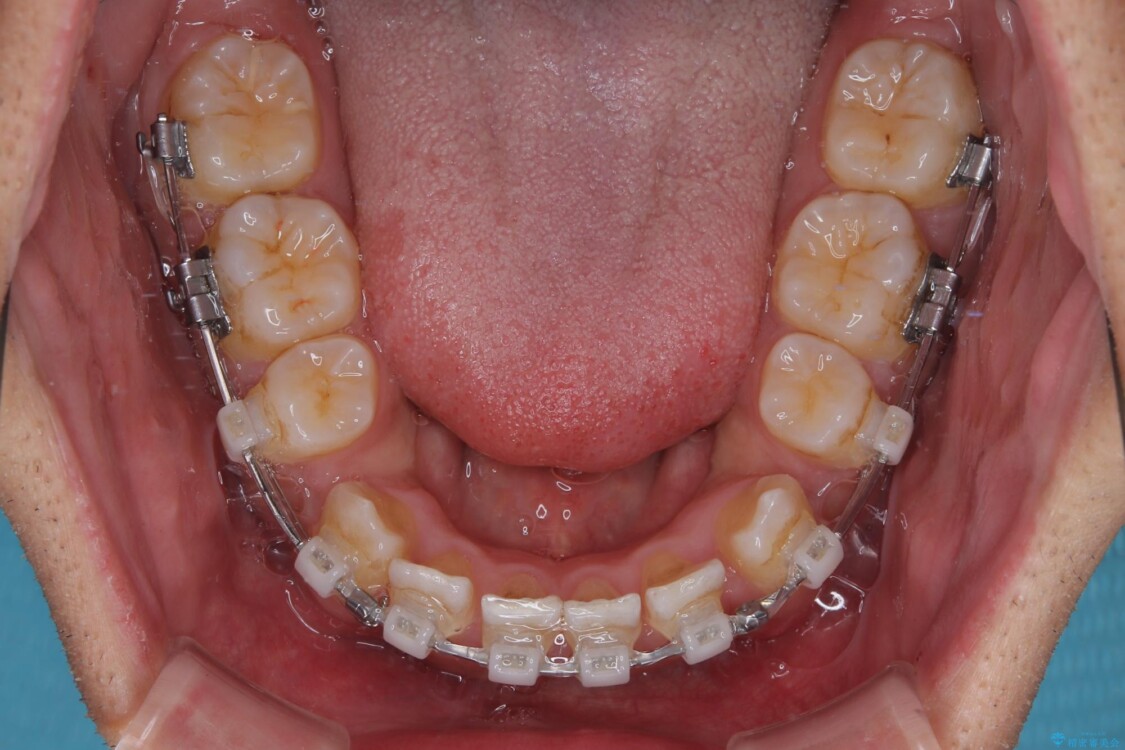

治療途中

• 八重歯と前歯のガタガタを抜歯矯正で治療|クリアブラケット使用例 治療途中画像

矯正装置は、審美性と費用面のバランスを考慮して、プラスチックブラケットとメタルワイヤーを使用しました。

透明感のあるブラケットを用いたため、従来の金属装置よりも目立ちにくく、日常生活での見た目の不安も軽減できます。